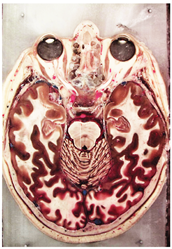

Table 2, Table 3, Table 4 and Table 5 present the results obtained through the multi-objective optimization image enhancement approach. Specifically, Table 2 and Table 3 show the results for natural images, while Table 4 and Table 5 display medical images. The tables are organized as follows: the first and second columns list the image names and their corresponding original, unenhanced versions. The third to fifth columns showcase the selected points from the Pareto front, representing the maximum contrast, knee point, and maximum detail, in that order. The final column illustrates the obtained Pareto front through the optimization process, with red, green, and orange points indicating the images that achieved maximum contrast, knee point, and maximum detail, respectively.

Table 4.

Medical image results—1.

As observed in the results, the images extracted from the Pareto front significantly maximize contrast and detail compared to the original images. In all study cases, the original image is dominated by the solutions extracted from the fronts, demonstrating the approach’s effectiveness in improving visual quality. However, the differences among the three enhanced images for each problem require a more detailed analysis.

For medical images, there are instances where differences are more perceptible. For example, in the Medical3 image, the maximum contrast solution makes it difficult to visualize the internal details of the basophil (a white blood cell highlighted in the box), which could result in a less accurate interpretation. In contrast, the knee and maximum detail solutions provide a clearer view of the interior of the white blood cell. Similarly, in the Medical5 image, the maximum contrast solution highlights the hand and arm bone structures. However, the maximum detail image offers a more precise view of the internal structures within the bones (see the highlighted region), which is crucial for a more detailed evaluation. Another notable example is the Medical8 image, where the maximum detail solution offers a more detailed view of the internal structure of the eosinophil (another type of white blood cell). However, the maximum contrast image improves the visibility of red blood cells. As shown in the yellow box, this solution reveals a red blood cell that is nearly imperceptible in the other solutions. An interesting case is the Medical6 image, where only a few non-dominated solutions are present on the Pareto front. Despite the similarities among the preferred solutions, the nodules are much more perceptible in the enhanced images than in the original image, as observed in the highlighted region.